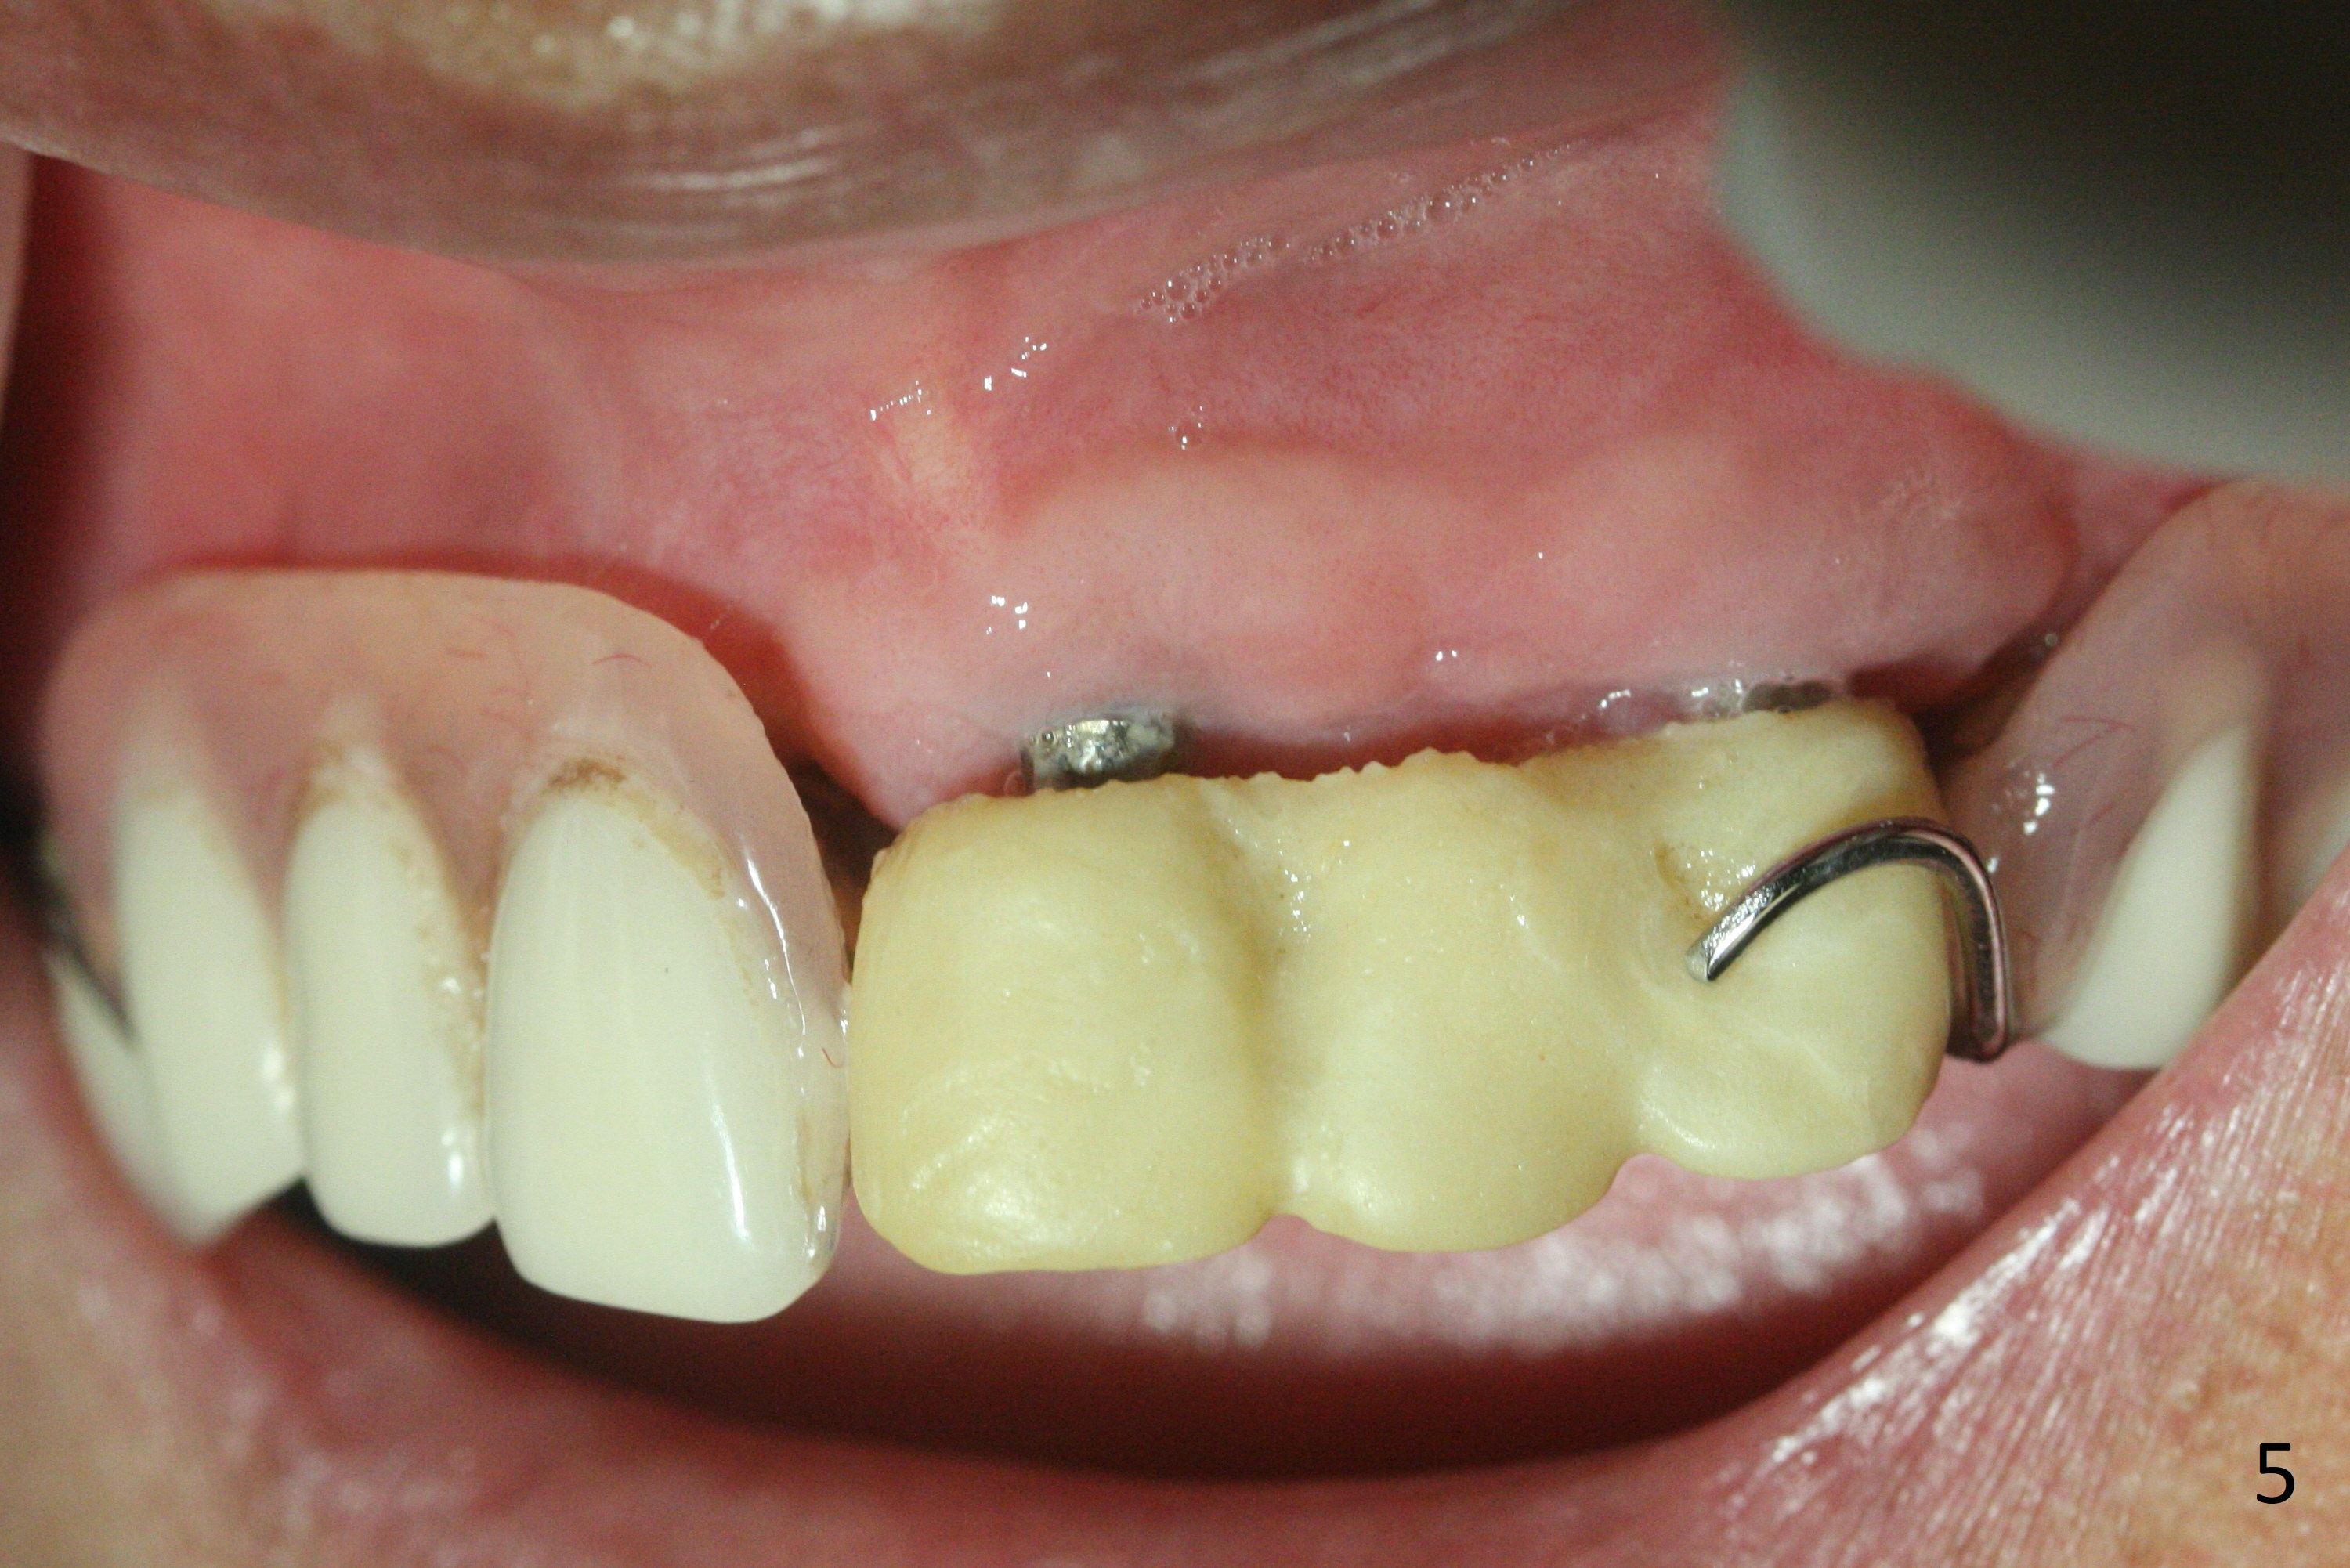

Incision reveals that the ridge at #9 and 11 is narrower than expected. A 3x14 mm 15º 1 piece implant is placed at the site of #9, while a 3x17 mm straight 1-piece one is placed at #11 (Fig.1,4). Insertion torques at #9 and 11 are 20 and 30 Ncm, respectively. The relatively low insertion torque is partially due to osteoporosis. The 65-year-old lady also has dry mouth. Osteotomy should be underprep. The position and trajectory of the implants are dictated by the partial denture (Fig.2). After minor abutment adjustment (Fig.3), an immediate provisional bridge is fabricated. There is no interference when the partial is removed and inserted. After bone graft (Fig.4 ^) and Osteogen Membrane, the ridge (Fig.3) is wider than before. The patient returns for reline 2 months postop (Fig.5-7). In spite of insufficient oral hygiene, the gingiva remains healthy around the implants. To form distinct papillae, acrylic should be added to (Fig.8 yellow line) and removed from (hushed area) the individual provisional crowns. One month after provisional modification (Fig.10, as compared to Fig.5), the pontic recipient site is concave (Fig.11) and becomes less concave after cord packing and abutment trimming. When the provisional bridge is reseated after impression (Fig.12), the pontic recipient site must be blanched again. Please trim the pontic recipient site of the model ~ .5 mm to enhance cosmetics. Water Pik has been used since surgery, but it may be related to loss of bone graft 3.5 months postop (Fig.9 *). One month post cementation, the patient has complained of pain when water pik is irrigating the gingiva palatal to the FPD, apparently in association with denture-related Candidiasis. Two weeks of use of Mycostatin Oral Suspension, peri-implantitis or peri-implant mucositis-like signs and symptoms disappear (Fig.13). CBCT taken 6 months postop confirms that the implants appear to be have been placed in the bone (14,15). The FPD appears to be loose 2.5 years post cementation.